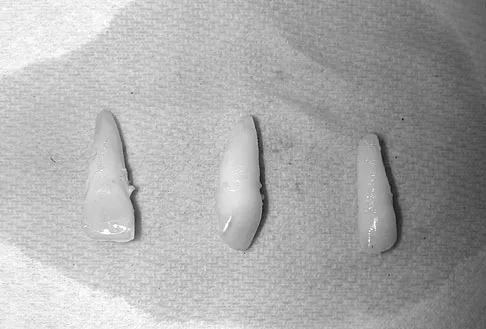

An 83-year-old woman reports pain in her left middle finger after a minor injury. Laboratory studies show a WBC count of 7,000/mm3, an erythrocyte sedimentation rate of 3 mm/h, a uric acid of 10.4 mg/dL, and a normal serum protein electrophoresis. Radiographs are shown in Figures 49a and 49b. A core biopsy specimen is shown is Figure 49c. In addition to treatment of the finger fracture, treatment should include

Explanation

This clinical picture is most consistent with periarticular erosions from gout. The patient has multiple periarticular lytic lesions in the hand. The laboratory studies show an elevated serum uric acid level, and the biopsy specimen demonstrates acute and chronic inflammation with prominent clefts. Therefore, the preferred treatment is systemic control of her gout. Radiation therapy, chemotherapy, and/or amputation should be considered for a malignancy; however, the pathology does not demonstrate any evidence of pleomorphism, high nuclear-to-cytoplasmic ratio, nuclear atypia, or mitotic activity. Antibiotics for an infectious process is a consideration, but the minimal elevation in the WBC count and erythrocyte sedimentation rate does not support an infectious process. Wise CM: Crystal-associated arthritis in the elderly. Clin Geriatr Med 2005;21:491-511.